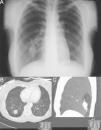

Mujer de 33 años remitida para valoración de riesgo pulmonar prequirúrgico ante cirugía abdominal laparoscópica por tumor ovárico izquierdo, hallazgo casual en su primera revisión ginecológica. Sin hábitos tóxicos ni antecedentes medicoquirúrgicos de interés, la paciente se encontraba asintomática y presentaba exploraciones física, analítica y funcional dentro de la normalidad, excepto que en las proyecciones anteroposterior y lateral de la radiografía de tórax se observaba una imagen polilobulada en el lóbulo inferior derecho (fig. 1). Los marcadores tumorales eran negativos. Mediante una tomografía computerizada torácica con contraste (fig. 1) se evidenció una lesión de 6,5×2,2cm, de morfología irregular, con varias prolongaciones en forma de dedos de guante, situada en segmento 10, acompañada de un área de radiolucencia segmentaria distal.

Posteriormente, se completó el estudio realizándose una broncofibroscopia que no evidenció lesiones endobronquiales ni anomalías en la segmentación de los bronquios hasta los límites accesibles con la técnica. De acuerdo con estos datos fue diagnosticada de una atresia bronquial congénita con broncocele distal del segmentario 10 derecho.

La atresia bronquial es una alteración caracterizada por la obliteración focal de una parte de un bronquio, que provoca acúmulo de secreciones y origina un broncocele con ausencia de ventilación del área pulmonar distal correspondiente (lo que radiológicamente se observa hiperlucente)3. Aproximadamente el 50% de los pacientes está asintomático en el momento del diagnóstico; se presenta con mayor frecuencia en varones (2:1), generalmente jóvenes4. La tomografía computerizada torácica con contraste es diagnóstica3, permitiendo diferenciar entre anomalías congénitas, bronquiectasias u otros tipos de obstrucción bronquial. El tratamiento en los pacientes asintomáticos es conservador; solo sería necesaria la cirugía en caso de aparecer síntomas (como infecciones respiratorias recurrentes, tos crónica y disnea)3.